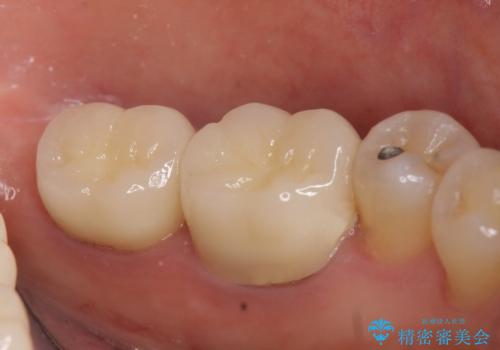

- 左下の奥歯が激しく痛むので診て欲しいといらっしゃった方の症例です。

左下7番目の歯に根尖病変を認めたため、再根管治療を行いました。

症状の消失を確認後、オールセラミッククラウンによる補綴を行いました。

今回用いたオールセラミッククラウンは、ジルコニアフレームという白い素材の上にセラミックを盛っているため審美性が非常に高いのが特徴です。

またジルコニアは人工ダイヤモンドの材料にも使われているほど高い強度を持っており、そのためオールセラミッククラウンは審美性だけでなく、奥歯やブリッジの補綴も可能とするクラウンです。